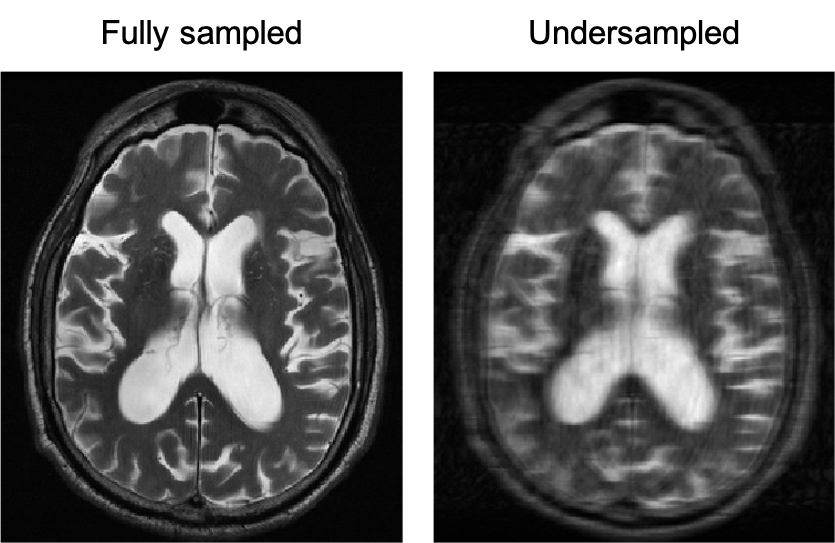

Undersampling is like painting a still life with a fraction of the paint you normally have at your disposal—or, with just a fraction of the time allowed to observe your subject. Thus, the algorithms that underlie an undersampling protocol must be well trained and well tested so that the resulting MRIs retain their diagnostic value.

Image 3. A fully sampled versus a 4X undersampled MRI of the brain. Courtesy of Florian Knoll.

To develop algorithms that could successfully reconstruct an undersampled MRI image, Dr. Knoll’s team needed a large dataset of fully sampled MRI images and associated raw data, referred to as k-space data, and a storage and distribution mechanism that would scale with the growth and demand of the dataset. They applied to the AWS Open Data Sponsorship Program (ODP) for their storage and distribution needs. They collaborated with Facebook AI for Research (FAIR) for their expertise in artificial intelligence (AI) and machine learning (ML), and began what would become an effort spanning countries and industries: FastMRI.